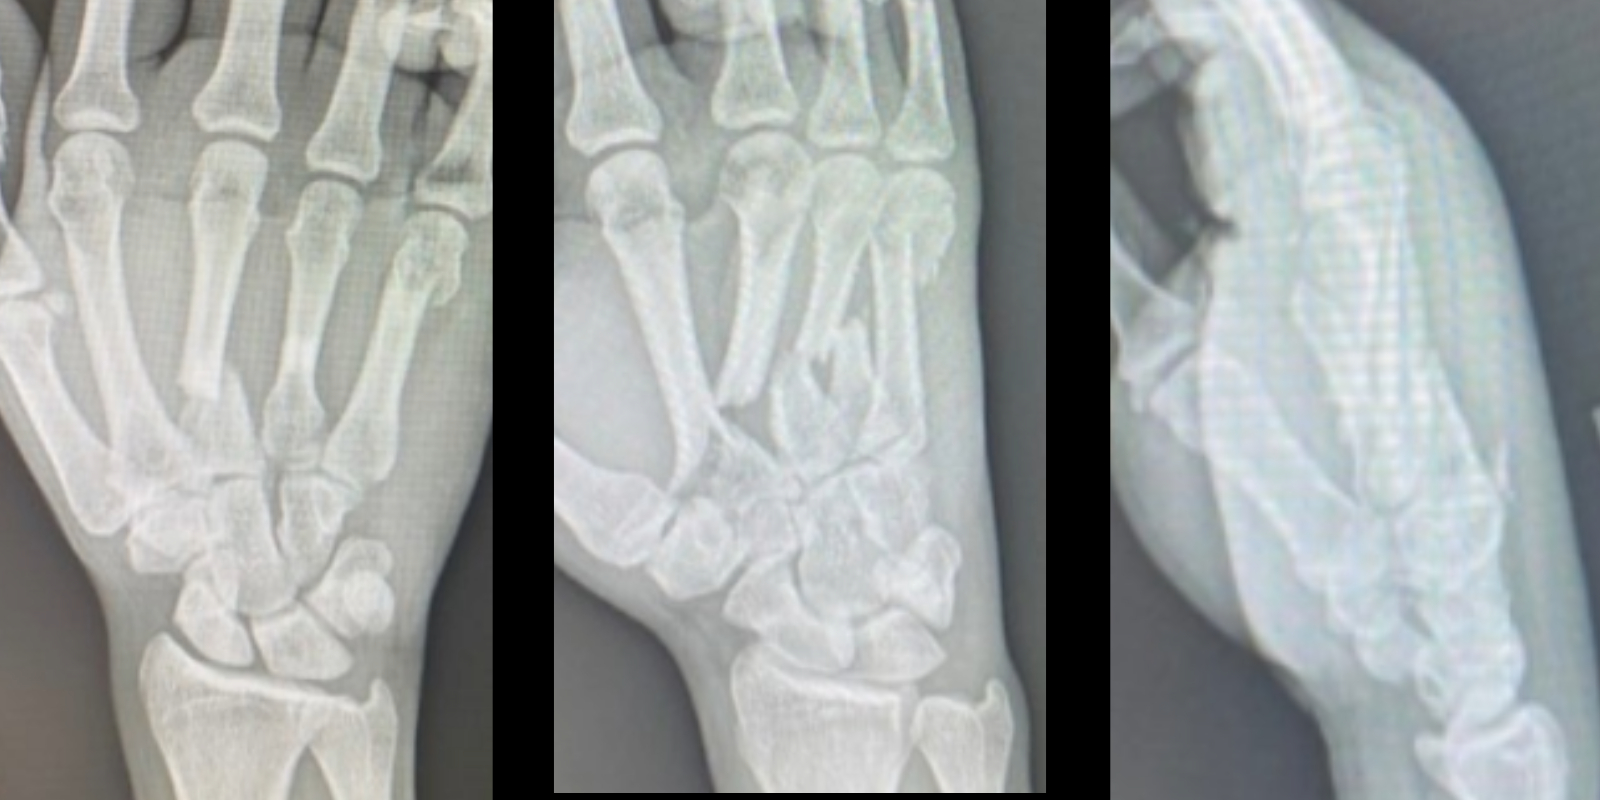

A 36-year-old right-hand dominant man presented with right-hand pain and deformity after falling from a motorized bicycle at moderate speed. Radiography revealed a nondisplaced oblique fracture of the second metacarpal base, a displaced transverse fracture of the third metacarpal base, a midshaft transverse fracture of the fourth metacarpal, and a neck fracture of the fifth metacarpal (Figure 1).

Figure 1: Preoperative radiographs of anteroposterior, oblique, and lateral views. Note the nondisplaced oblique fracture of the second metacarpal base, a displaced transverse fracture of the third metacarpal base, a midshaft transverse fracture of the fourth metacarpal, and a neck fracture of the fifth metacarpal.